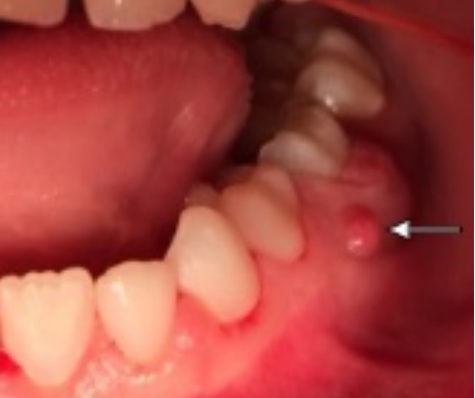

牙龈脓肿

症状表现

是指与牙齿相关的脓包。是软的,孤立的丘疹,位于牙床上端。

图片来源:[2]

如何处理

带宝宝去口腔科就诊,进行口腔治疗,以减少和消除组织的发炎。